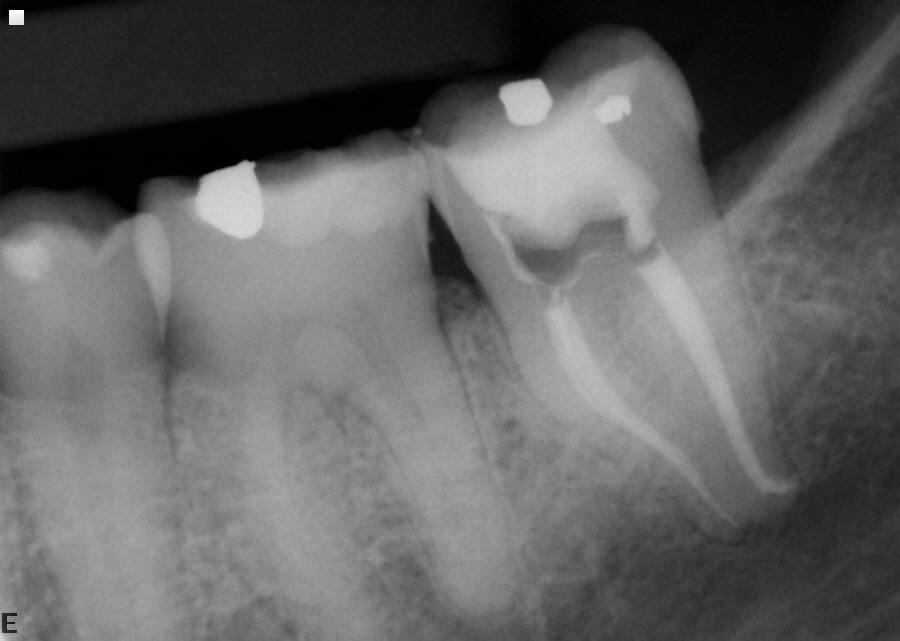

Case 70 Three Definitive Mesial Canals

Pre-Op Xray #30

Post-Op Xray #30 (polarized xray)

Comment: Need I say anything?

Usually a "3rd canal" goes into either the mesial lingual or mesial buccal canals on a lower molar.

Occasionally, there are 3 separate canal systems in the mesial root of lower molars.

If you have properly cleaned the mesial lingual and mesial buccal canals and they are dry,

but there is exudate between the two, it usually means a 3rd canal is present.